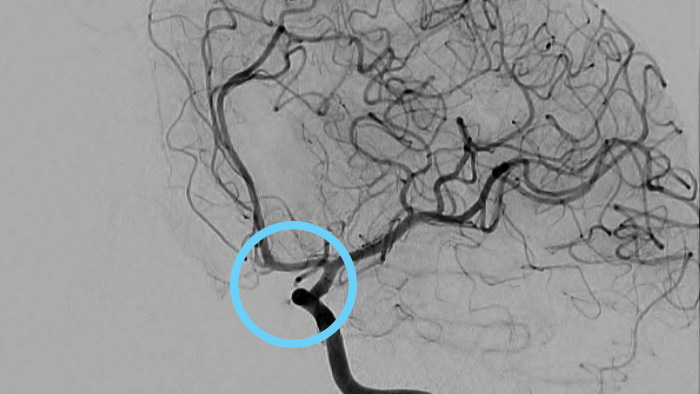

Fall mit freundlicher Genehmigung von Prof. Laurent Spelle, Hôpital Bicêtre, Paris, Frankreich

Patient:

16. Juni 2014

19. Dezember 2014

Bei der Planung der Behandlung eines zerebralen Aneurysmas stehen Sie vor drei wichtigen Herausforderungen: 1) Erlangen von Einblicken in komplexe Gefäßstrukturen, 2) Genaue Beurteilung von Position, Größe und Hals des Aneurysmas, 3) Feststellen und Verifizieren, ob die Schwere der Läsion eine Intervention erfordert und ob genug Informationen zur Verfügung stehen, um einen geeigneten Behandlungsplan zu erstellen.

3D-RA liefert in wenigen Sekunden eine volumetrische Darstellung und unterstützt so die Beurteilung von Position, Größe, Hals und Schweregrad des Aneurysmas für die Behandlungsplanung. Darüber hinaus bietet 3D-RA Volumendaten mit hoher räumlicher Auflösung und gleicht Patientenbewegungen automatisch aus.